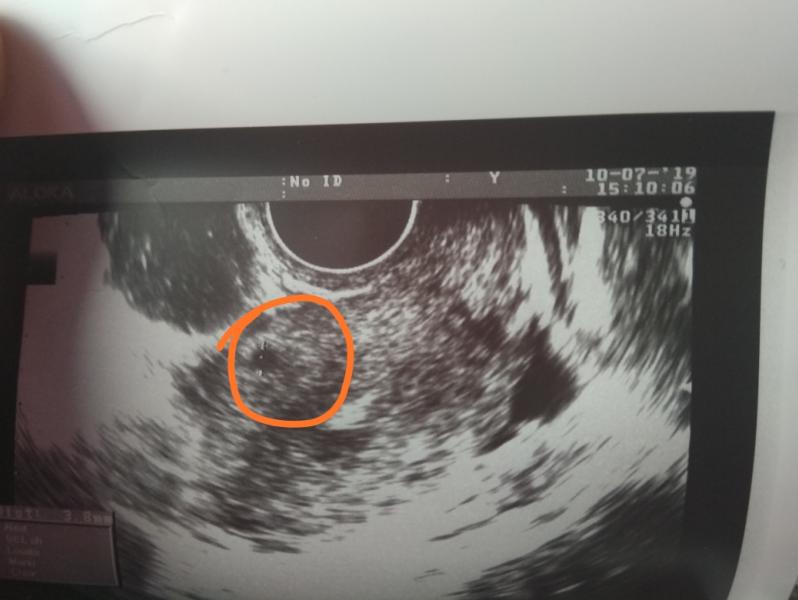

В связи с тем что у меня задержка в 3дня вчера была и было много признаков на Б. Я посетила гениколога и она сделала мне УЗИ. На этом УЗИ обнаружила черную точку в матке,в размере 4мм. Но в выписке написала что это плодное яйцо,но явка на повторное УЗИ через 10 дней.